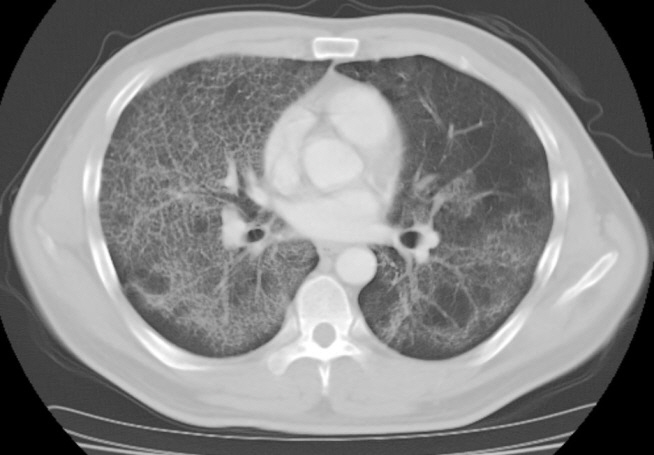

Whole lung lavage using a rapid infusion system to treat a patient with pulmonary alveolar proteinosis

Whole lung lavage (WLL) is a therapeutic procedure to remove accumulated material by infusing and draining the lungs with lavage fluid. This procedure has been regarded as the current standard of care to treat pulmonary alveolar proteinosis. However, the WLL protocol has not yet been standardized and the technique has been refined and modified a number of times. A rapid infusion system is a device used to infuse blood or other fluids at precise rates and normothermic conditions. This device is not typically used in WLL, which relies on the passive infusion of fluids using the gravitational force. However, in this study we performed WLL using a rapid infusion system, since we aimed to take advantage of its shorter operation time and greater degree of control over fluid volume and temperature. The patient’s symptoms improved without the occurrence of any complications.